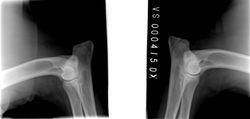

Figaro from Eagle Hills

*10. 2. 2015Dobrý rámec, silná kostra, výborná hlava, nůžkový skus, pěkný hrudníkVýška: 72cmVáha: 68kgHD B, ED 0/0, OCD Neg, DOV vyšetření prostýOcenění: Speciální a klubová výstava Přerov štěně VN1, MVP Praha dorost VN1, MVP Praha dorost VN1, MVP Č. Budějovice V1 CAJC, MVP Praha V1 CAJC BOJ, 50. ročník MVP Intercanis Brno V1 CAJC, 24. 3. 2017 Český Junior Šampion, MVP Č. Budějovice CAC CACIB BOB, 52. Ročník MVP Intercanis Brno V2 res. CAC, KV Mladá Boleslav V1 CAC